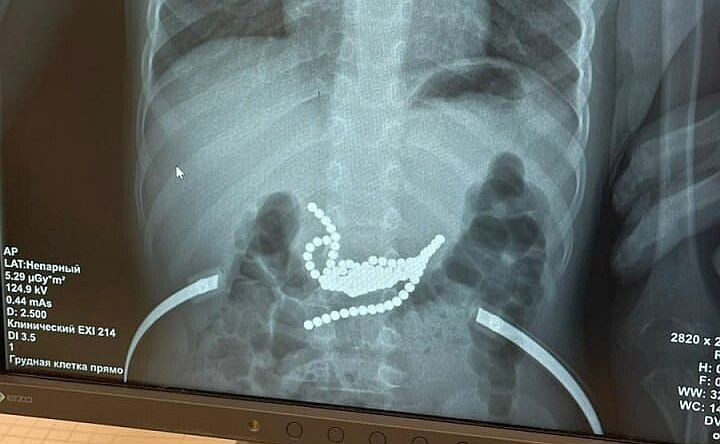

В Ростове спасли малыша, который проглотил 50 магнитных шариков

Хирурги Ростовской областной детской клинической больницы достали из желудка мальчика 50 магнитных шариков. Как оказалось, родители купили мальчику магнитные шарики, чтобы играя в них, малыш развивал мелкую моторику, но ребёнок их съел.

Эндоскопическая попытка извлечь магнитные шарики оказалась безуспешной. И в итоге потребовалась очень полостная операция.

По словам одного из хирургов, который оперировал ребёнка, Антона Штарева, магнитные шарики были неодимовые, у них самая большая сила магнетизма.

«Основная часть магнитов находилась в желудке, другие — в тонкой кишке, поэтому, чтобы извлечь все магниты, пришлось вскрывать просвет и кишки, и желудка. В этом сложность и уникальность операции. Если бы родители обратились в больницу на пару часов позже, могла бы произойти перфорация, и тогда последствия для здоровья малыша были бы гораздо более тяжёлыми», — рассказал хирург.